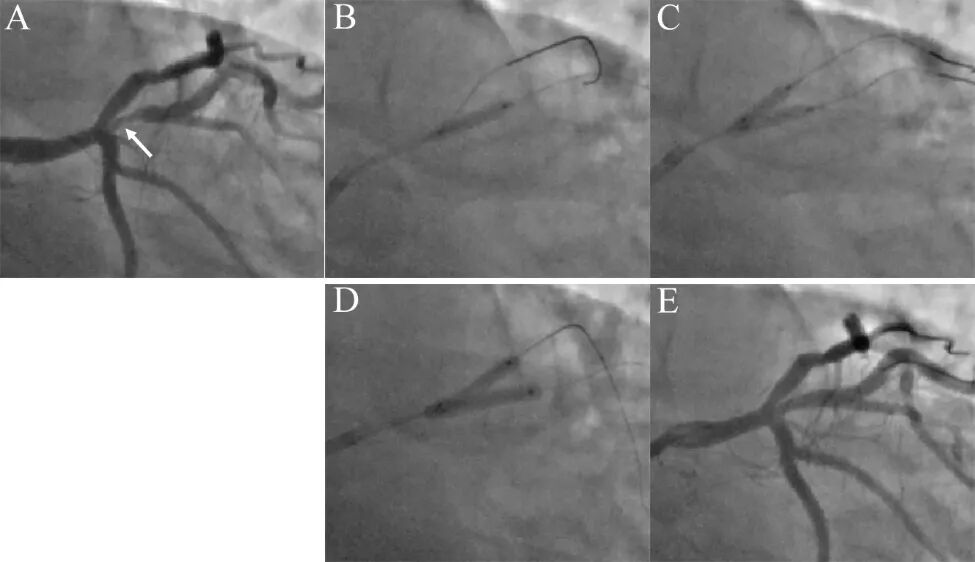

图5 球囊对吻处理中间支开口病变。

图4同一病例11个月后,再次出现劳力性心绞痛,性质同前。复查造影提示中间支开口病变再次加重至90%(A)!分析再狭窄原因,可能与前降支扩张时斑块移位和脊移位有关,也可能与中间支未充分扩张导致斑块弹性回缩有关。决定采用球囊对吻技术,首先2.75×10mm切割球囊预处理病变(B),然后两个2.75高压球囊8atm×20秒对中间支和前降支对吻扩张(C),最后2.75mm×15mm药物球囊12atm×45秒对吻扩张(D),造影结果良好(E)。IVUS检查前降支开口和中间支开口MLA 分别为5.5 mm2和5.6 mm²。随访2年未有心绞痛再发。